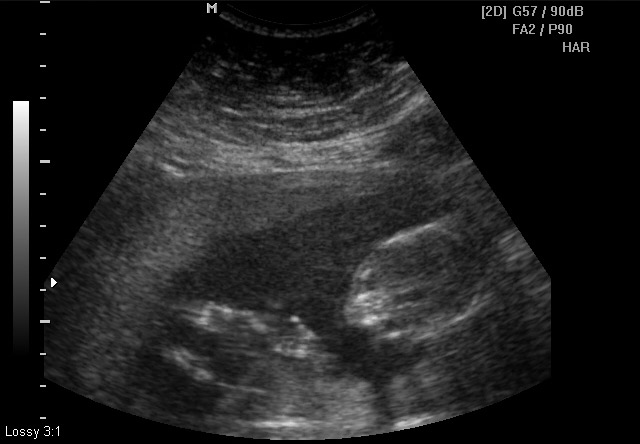

The ultrasound tech kept referring to the baby as "he/him"... but, they don't make gender determination until 18 weeks. Anything that can be gleaned from these?

Attachment 15430Attachment 15431Attachment 15432Attachment 15433Attachment 15434Attachment 15435